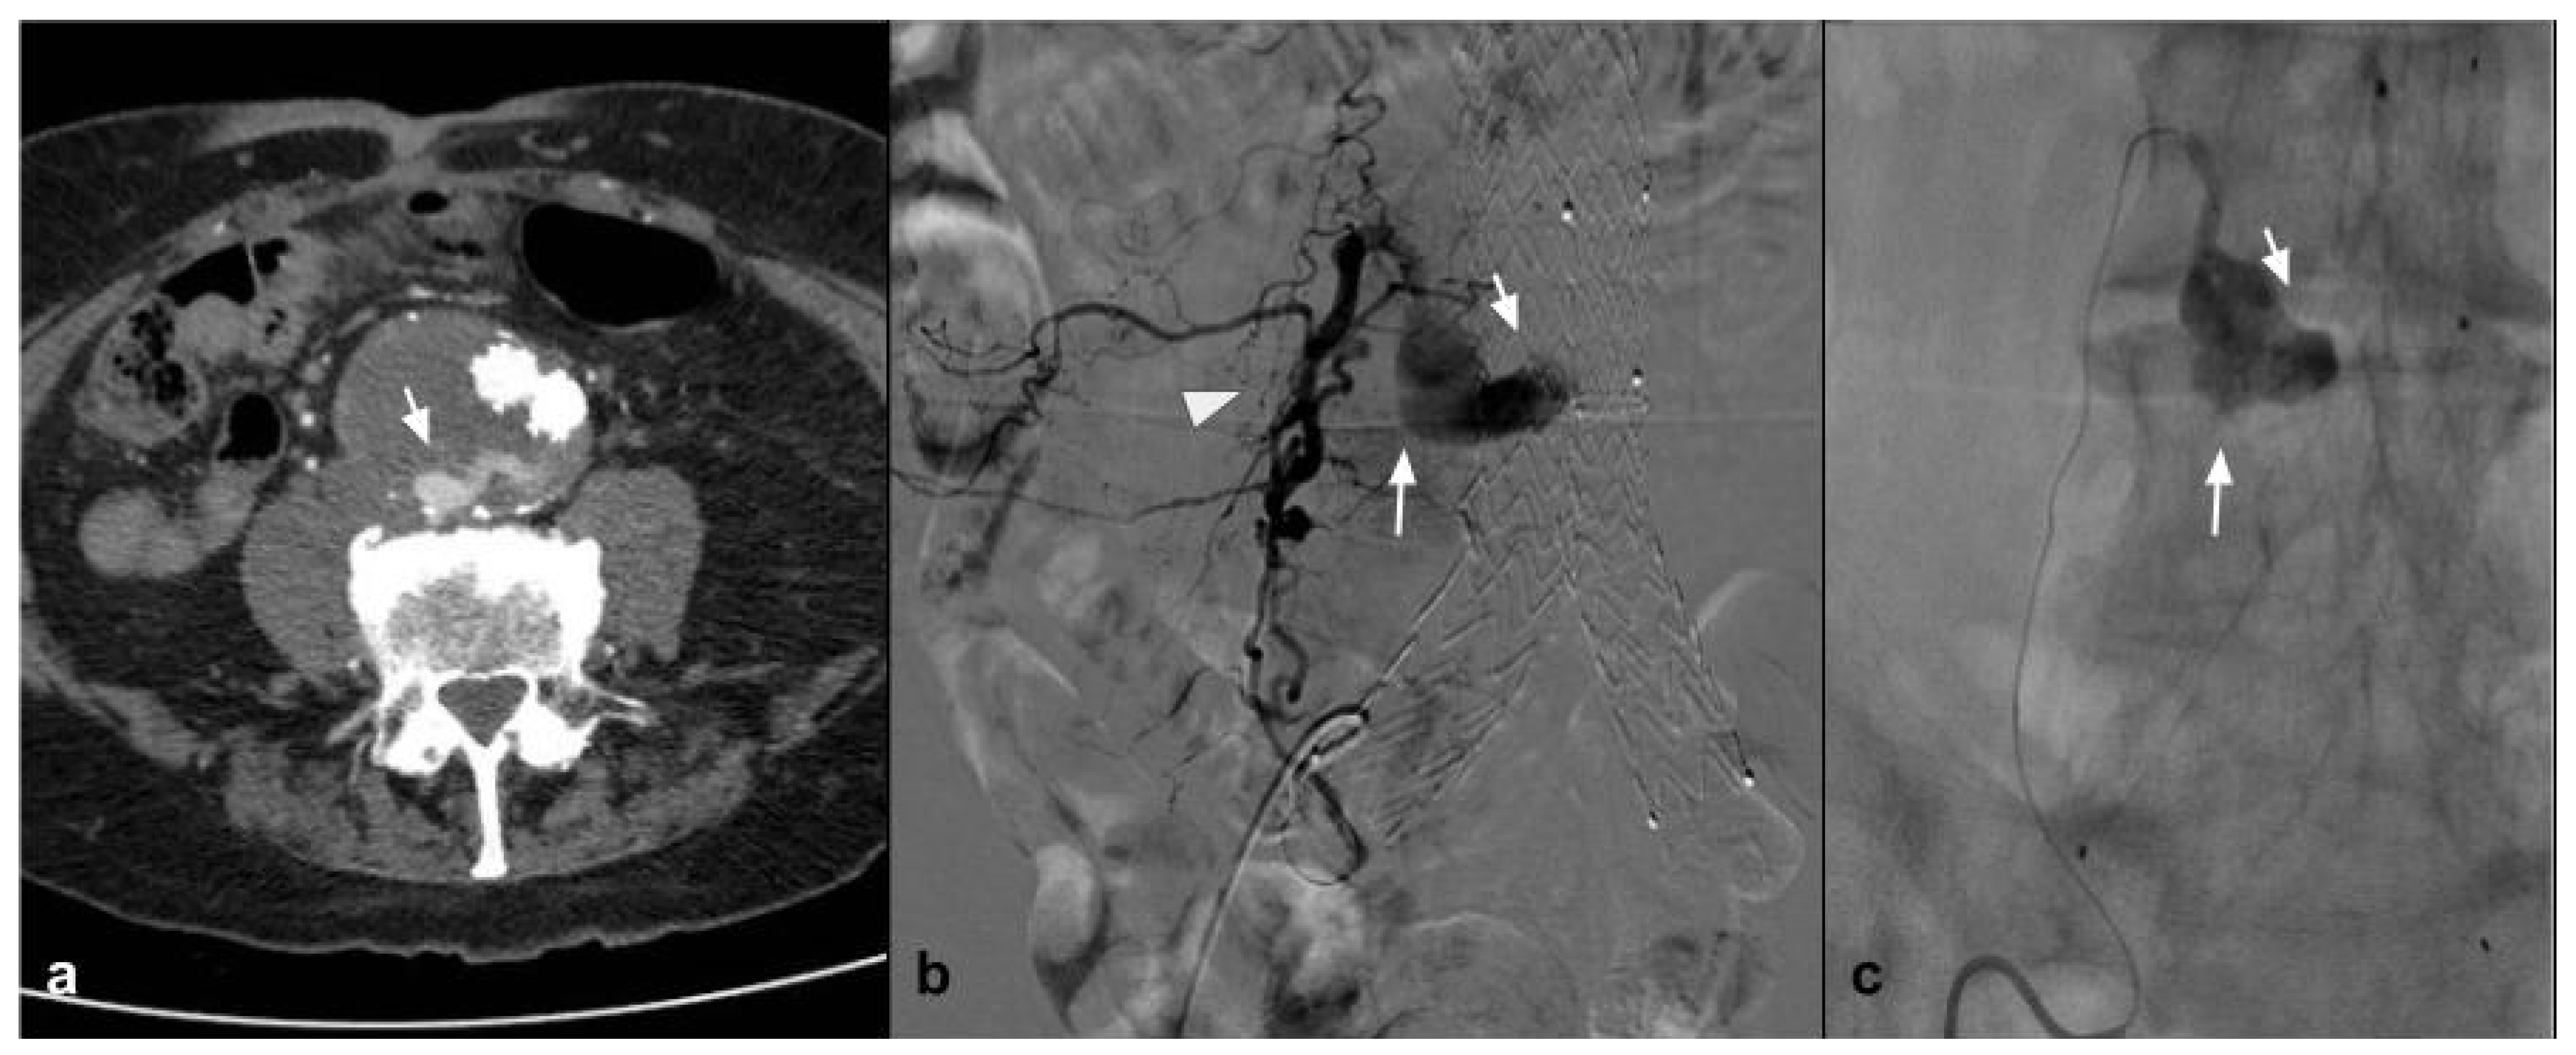

8. Visceral Aneurysms-Pseudoaneurysm

One condition that has been treated with NALEA is splenic aneurysm. A number of papers have recently been published demonstrating the possibility of embolization using NALEA in combination with coils. Both proximal and peripheral splenic aneurysms with different anatomical conformation have been treated in the literature [17,20] (Figure 4).

Figure 4.

(a) Coronal CTA MIP demonstrates post surgical pseudoaneurysm of left gastric artery (white arrows). (b) DSA performed with Simmons 1 catheter at the level of the ostium of the celiac trunk confirms the presence of the pseudoaneurysm (white arrow). (c) DSA performed with microcatheter in the left gastric artery highlights a saccular dilation (white arrow) of the left gastric artery with regular patency of the efferent vessel (black arrow). (d) Post-procedure DSA control demonstrates complete exclusion of the treated PSA (asterisk) with an Onyx 18 cast completely occupying the malacic vessel performing an “endovascular ligature technique” (white arrow).

A second solid experience was published by Urbano et al. in 2017 [65], who performed in 22 consecutive patients and 25 lesions for symptomatic AMLs or AMLs > 4 cm. Mean AML size in this study was 7 cm. In this study, the peculiarity is that EVOH copolymer was the only embolic agent used. A postembolization syndrome was scheduled in 18.5% of patients, maybe because, when using only Onyx, a large quantity of EVOH was injected. Also for Urbano et al., AML embolization with EVOH copolymer is feasible, safe, and effective (Figure 5).

Figure 5.

(a) Coronal CTA MIP highlights a large angiomyolipoma of the right kidney lower third (white arrow). (b) DSA performed with a direct injection in the right renal artery confirms the lesion with an abnormal arterial vascularization (black arrows). (c) A post procedure DSA check demonstrates the presence of the Squid 34 cast which completely occludes the tributary arteries of the lesion (white arrows) and preservation of the healthy renal parenchyma (black arrows).